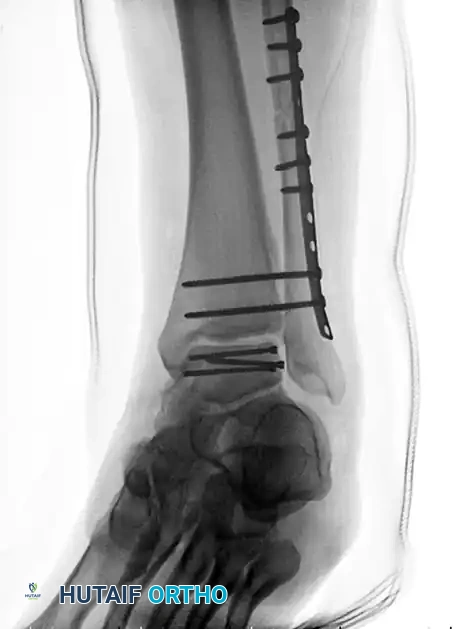

Image

FIGURE 88-42 C: Concurrent fixation of the fibula with a neutralization plate and screws. Failure of such constructs often leads to the salvage pathways discussed herein.